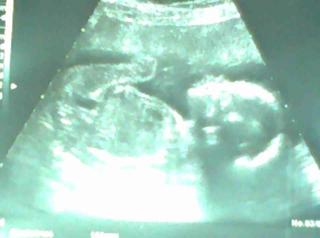

Jinak z tý ultrazvukoví fotky jsem uplně nadšená, už jich máme hromadu a vždycky to je jenom rozmazané cosi 😀 a tady je uplně úžasně. Už má 398 gramů a od hlavičky po zadeček 16,3 centimetru 😉